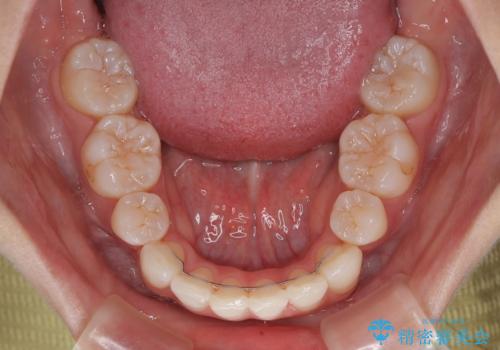

下唇に前歯が当たって跡が残ってしまう状態でしたが、スッキリとした口元に仕上げることができました。

- 口を閉じたときに飛び出してしまう上顎前歯を気にして来院された患者様です。

下顎はデコボコが気になっていたため、上下左右第一小臼歯4本を抜去して、ワイヤー装置にて口元の突出感を改善するよう矯正治療を行うこととしました。